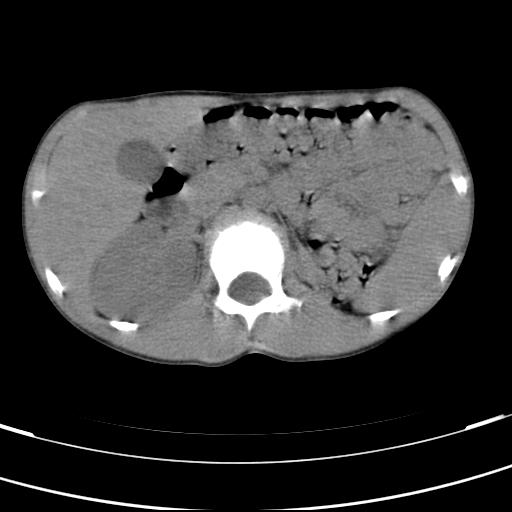

标题: PED3157:左肾缺如,请教脾脏的改变?、、

男孩,9岁。胃部不适。

脾脏位于左侧,但数个脾脏呈分离状态,左肾缺如,右肾代偿肥大。考虑多脾综合征。